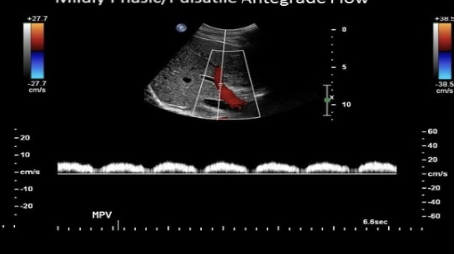

which describes normal doppler waveform in the portal vein

.

a) mild pulsatility w/respiratory variation

b) blunted w/respiratory variation

c) prominent respiratory variation + mild pulsatility

d) moderately pulsatile flow due to vessel proximity to heart

a. mild pulsatility w/respiratory variation